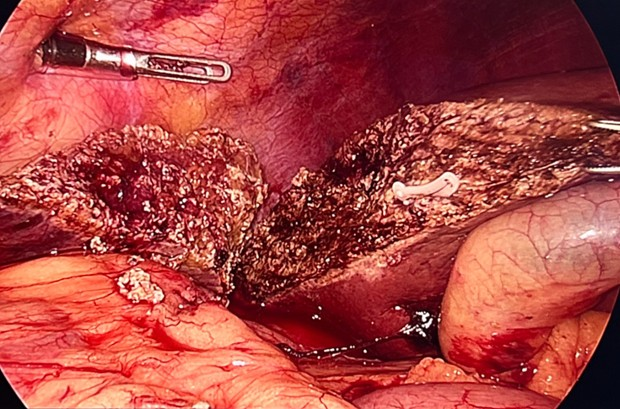

* Trường hợp số 1: bệnh nhân Nguyễn Đức H, nam, 51 tuổi, được chẩn đoán ung thư trực tràng di căn gan. Kết quả sinh thiết khối u trực tràng là ung thư biểu mô tuyến, không có đột biến gen KRAS hay BRAF, cũng như không bộc lộ gen dMMR. Thông qua hội chẩn đa chuyên khoa, bệnh nhân được hóa trị tiền phẫu theo phác đồ hóa chất kết hợp điều trị đích CapeOX + Bevacizumab và đánh giá lại sau 5 chu kỳ. Kết quả cho thấy bệnh nhân đáp ứng tốt với điều trị, thể hiện trên nội soi (hình 1), cắt lớp vi tính (hình 2) và cộng hưởng từ, khối u giảm kích thước, tổn thương gan khu trú tại hạ phân thùy 6 kích thước 34 mm (đánh giá giai đoạn u là cT4N2M1 trước điều trị hóa chất và ycT4N0M1 sau điều trị hóa chất). Bệnh nhân đã được tiến hành phẫu thuật nội soi hoàn toàn cắt trực tràng, và toàn bộ mạc treo trực tràng qua đường hậu môn (Transanal Total Mesorectal Excision - TaTME) (Hình 3) (được thực hiện bởi kíp Phẫu thuật Ống tiêu hóa) kèm cắt u gan hạ phân thùy 6 (được thực hiện bởi kíp Phẫu thuật Gan mật). Hậu phẫu bệnh nhân ổn định, phục hồi nhanh, ra viện sau mổ 7 ngày.

Hình 3. Hình ảnh trực tràng kèm toàn bộ mạc treo và u gan hạ phân thùy 6 đã được phẫu thuật